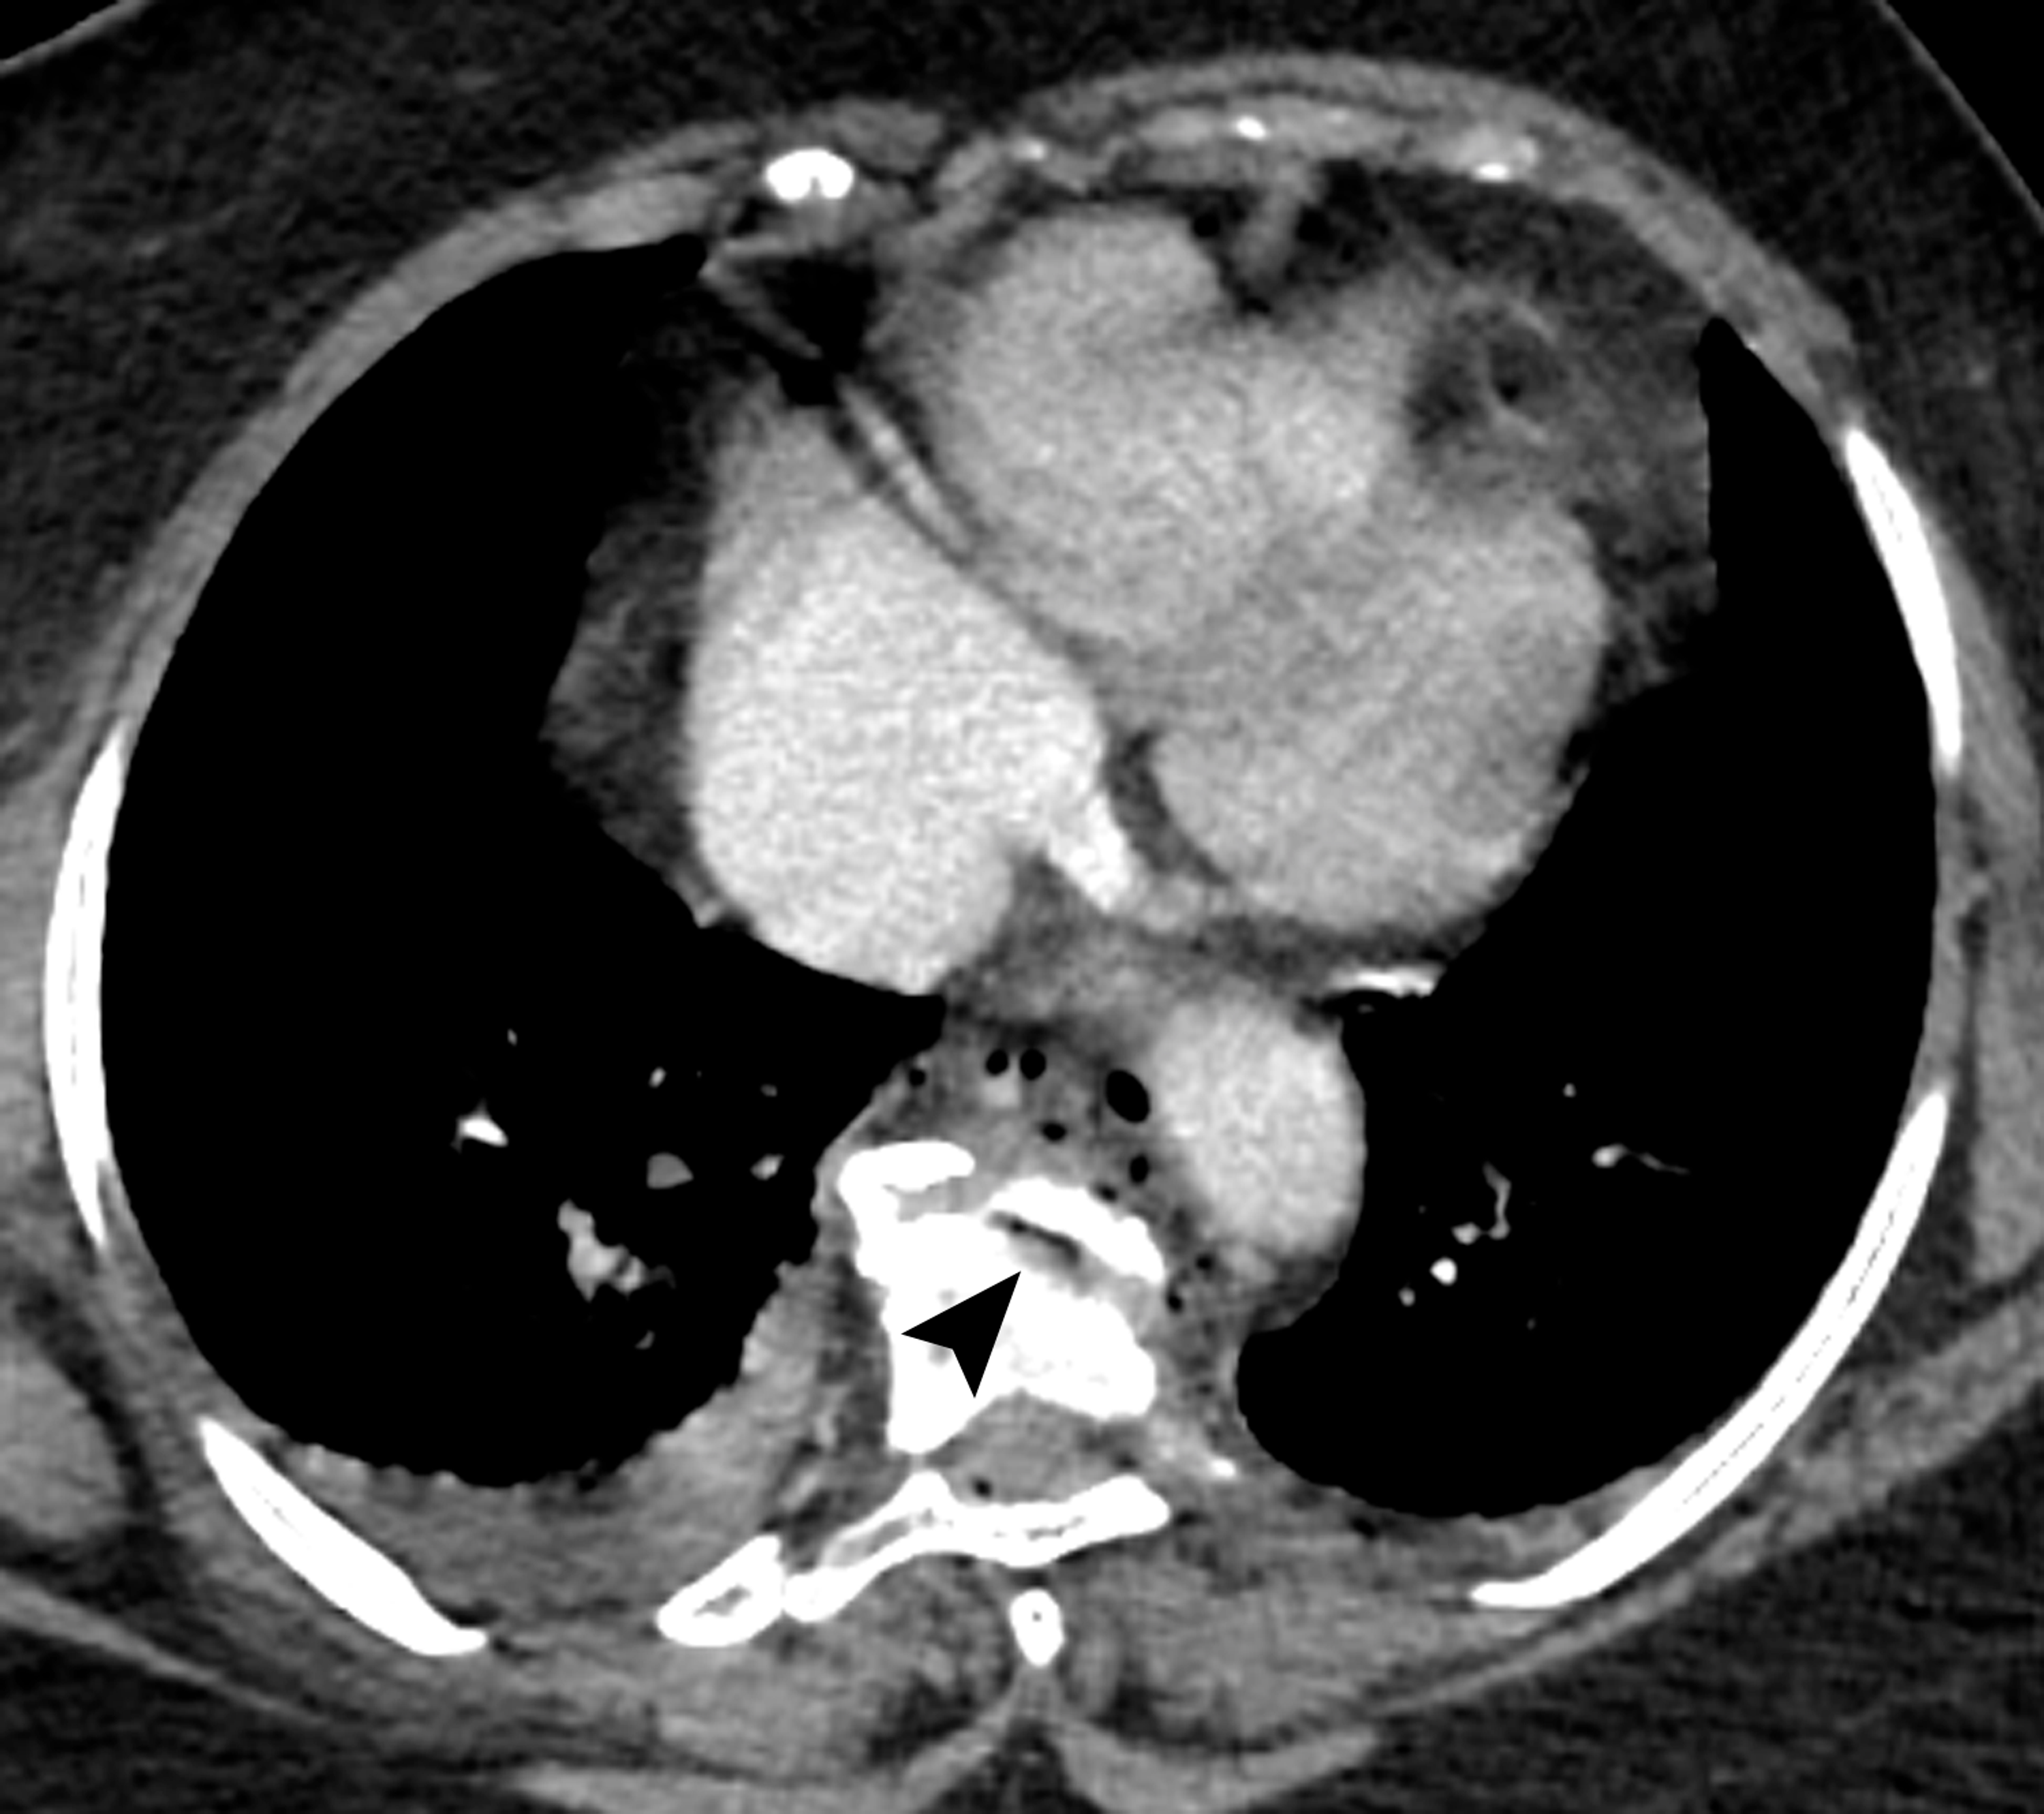

Cureus Pneumomediastinum From Vacuum Disc and Vertebral Trauma Vacuum Disc Phenomenon Treatment ‘vacuum phenomenon’ or ‘pneumoarthrosis’ term is used when there is air within a joint space. What is the treatment for degenerative disc disease? Surgical therapy is still an acceptable method for the treatment of. Vacuum disc phenomenon at multiple lumbar spinal levels with nitrogen bubbles (arrows) leaking into the spinal fluid. In cases of gas accumulation in the spinal canal,. Vacuum Disc Phenomenon Treatment.